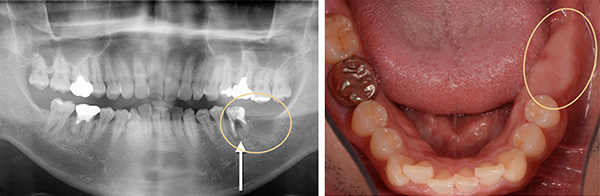

初診時:2020年 46才 男性. 左下大臼歯2本欠損

ワックス作業もデジタルに、神経確認でより安全なインプラント設計